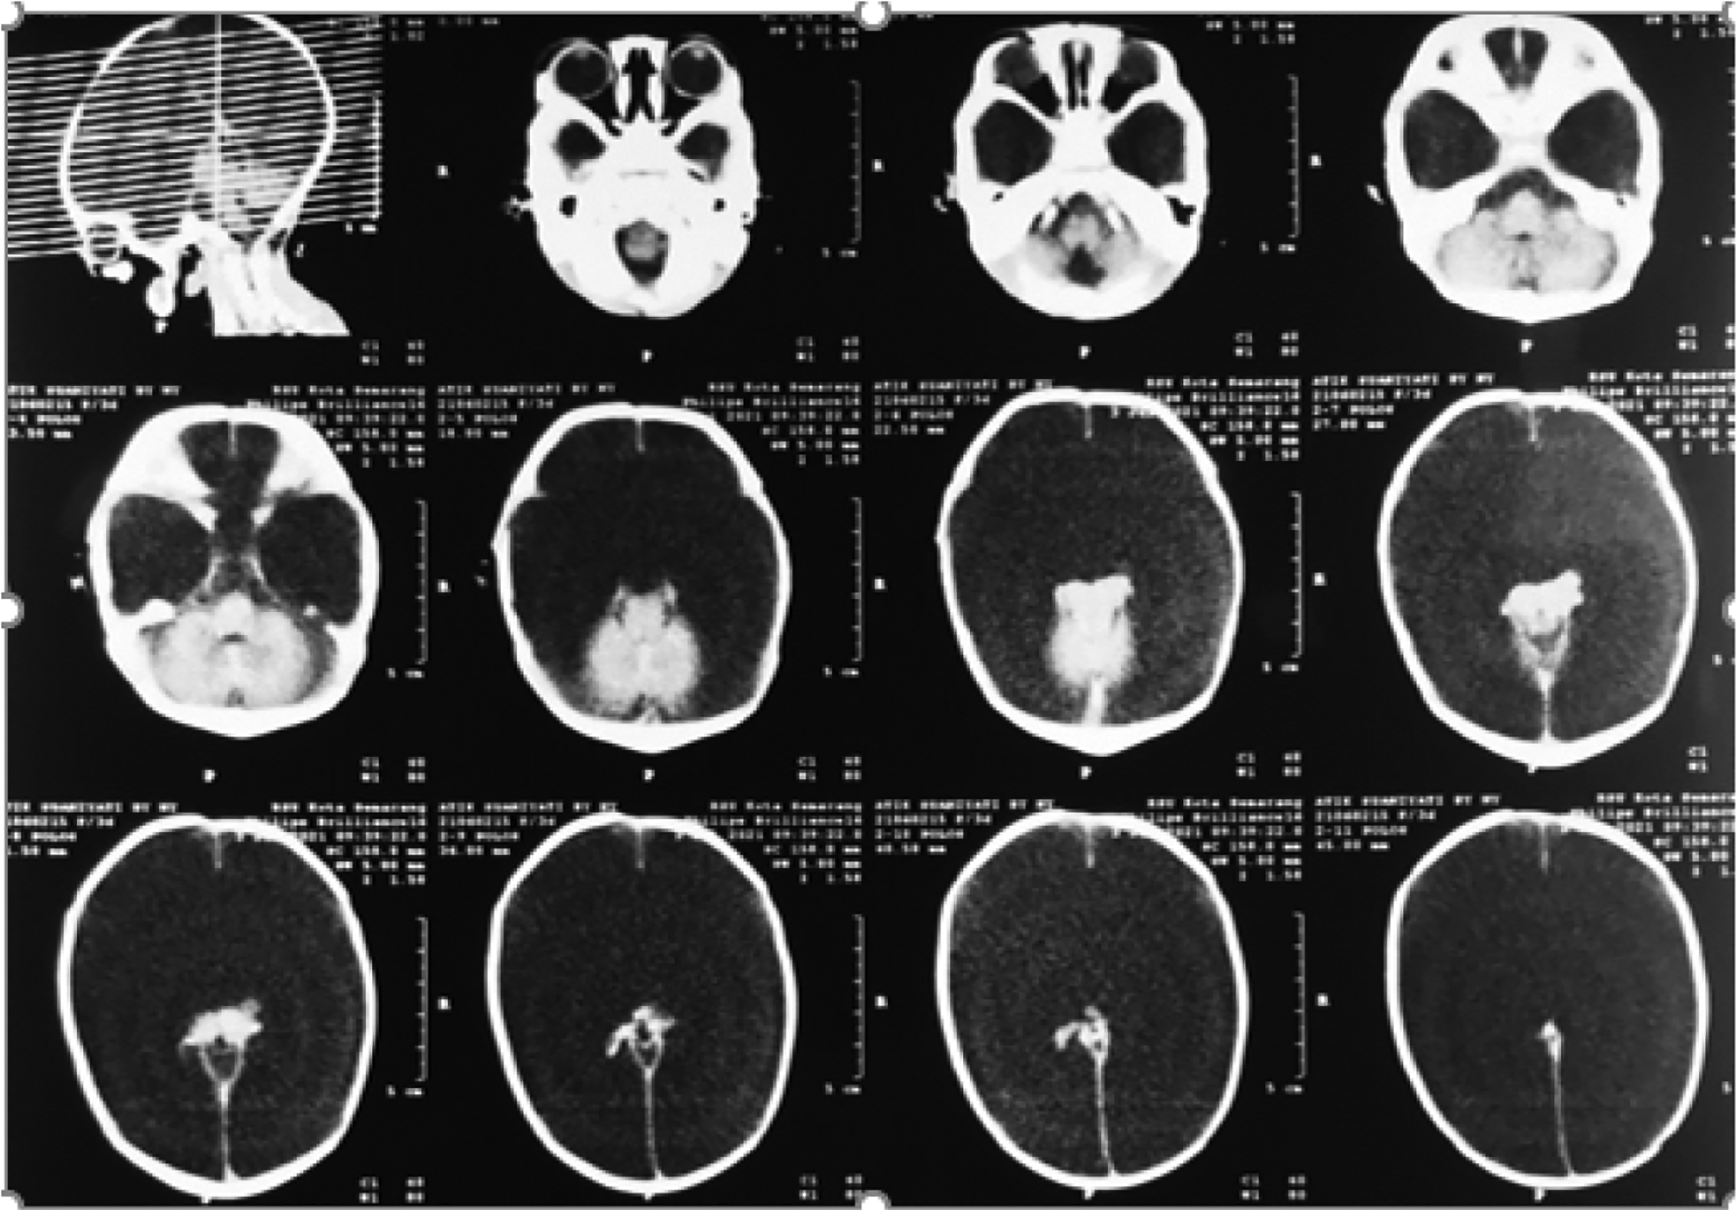

On the second day, the baby looked less active, moaned, showed acral cyanosis, and had a large fontanelle that was dilated and soft. Signs of hydrocephalus such as Macewen’s sign, setting sun phenomenon, and transillumination were found to be positive. From the babygram examination, neonatal pneumonia was suspected, while the echocardiographic examination indicated a floppy interatrial septum and mild mitral regurgitation (Figure 1). The non-contrast computerized tomography (CT) scan of the head showed a hypodense lesion according to the density of CSF filling the right and left hemicrania, while the hemi-cerebral cortex and lateral and third ventricles were not visible. Structures of the right thalamus, mesencephalon, pons and posterior fossa, and falx cerebri were still visible. The non-contrast CT scan of the head indicated hydranencephaly (Figure 2). From the toxoplasmosis, rubella, CMV, and herpes simplex virus (TORCH) screening examination, the results of anti-CMV immunoglobulin G (IgG) were 22 aU/ml (positive if the value ≥6) and anti-CMV IgM were 0.156 COI (negative if the value ≤0.7).

The structures of the right thalamus, mesencephalon, pons and posterior fossa, and the falx cerebri are still visible. CT, computerized tomography.